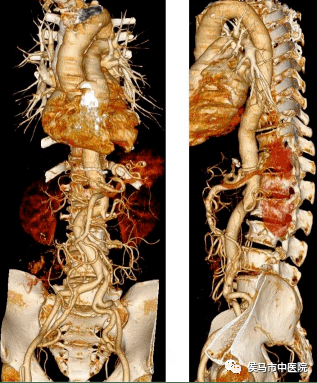

4、主动脉CTA

主动脉CTA可清晰显示主动脉系统的解剖形态及病变的部位、大小及范围,也能清晰显示主动脉管腔、动脉壁厚度、钙化、动脉瘤内附壁血栓的情况,临床主要应用于主动脉瘤、先天性主动脉发育异常、主动脉及分支狭窄闭塞疾病、大动脉炎、马凡综合症的诊断与鉴别诊断。